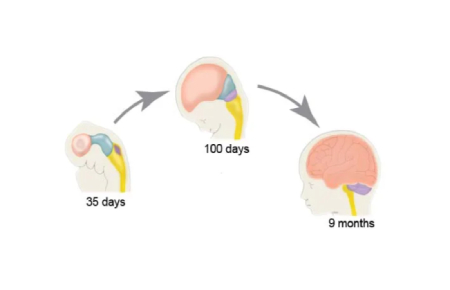

۱. رشد مغز نوزاد: یک فرآیند پیچیده و سریع

رشد مغز نوزاد از آغاز بارداری، یعنی از لحظه باروری، شروع میشود. در اوایل بارداری، سلولهای عصبی (نورونها) به سرعت تقسیم شده و در مراحل بعدی شروع به اتصال به یکدیگر میکنند. در این زمان، مغز نوزاد هنوز به اندازه یک دانه برنج است، اما شروع به ایجاد مسیرهای عصبی میکند که بعدها به مهارتهای مختلف مانند حرکت، زبان، و حافظه تبدیل خواهند شد.

در سه ماهه اول بارداری:

ساختار مغز در حال شکلگیری است و شروع به تشکیل قسمتهای مختلف خود میکند.

نورونها به سرعت در حال تقسیم و تشکیل اتصالات عصبی هستند.

در این مرحله، مغز نوزاد به طور کلی هنوز نمیتواند عملکردهای پیچیدهای انجام دهد، اما یک سری فعالیتهای ساده مانند حرکتهای ابتدایی عضلانی آغاز میشود.

در سه ماهه دوم بارداری:

مغز نوزاد شروع به فعالیتهای پیچیدهتری میکند. سیستم عصبی به شدت در حال گسترش است و این دوره یکی از مهمترین مراحل رشد مغز محسوب میشود.

در این مرحله، نوزاد قادر به انجام حرکتهای ابتدایی مانند تکان دادن دستها و پاها است.

سیستم شنوایی نوزاد در حال تکامل است و او شروع به شنیدن صداها از محیط اطراف، از جمله صدای ضربان قلب مادر و صدای محیط بیرونی، میکند.

در سه ماهه سوم بارداری:

مغز نوزاد به سرعت در حال رشد و تکامل است. در این دوره، بخشهایی از مغز که مسئول مهارتهای حرکتی، حافظه، و احساسات هستند، فعالیت بیشتری از خود نشان میدهند.

نوزاد شروع به واکنش نشان دادن به محرکهای بیرونی مانند نور و صدا میکند.

نوزاد قادر است چشمان خود را باز و بسته کند، به اطراف حرکت کند و در برخی موارد حتی مکیدن را آغاز کند.